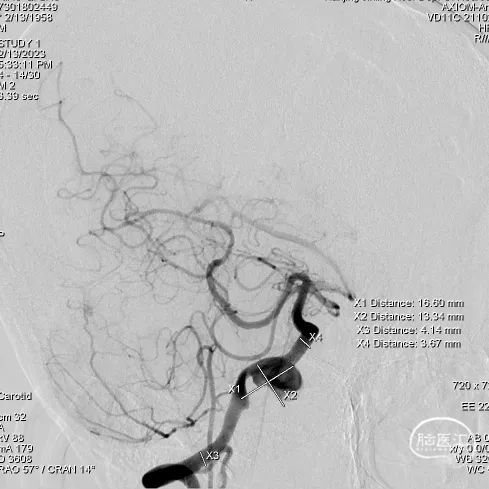

右侧颈内动脉造影

右侧椎动脉造影

长鞘到位后工作角度造影;尽量暴露双椎汇合部,方便术中判断支架头端锚定位置。